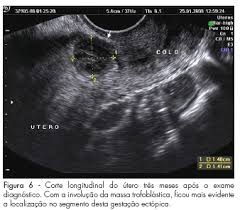

Gravidez Ectopica Na Cicatriz Uterina De Cesarea Relato De Caso